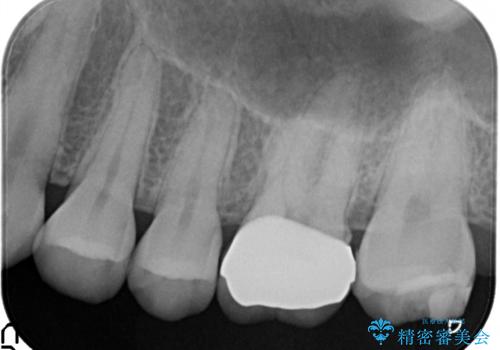

【メタルフリー】銀歯を白くしたい。オールセラミッククラウン。

- 銀歯を白くしたいと希望され来院されました。

すぐにでも白くしたいとのことで、2回目の来院で銀歯を白い仮歯に変更し喜んでいただきました。

ただ単純に白くするでけではなく拡大鏡を使用し、丁寧な処置を行なっております。